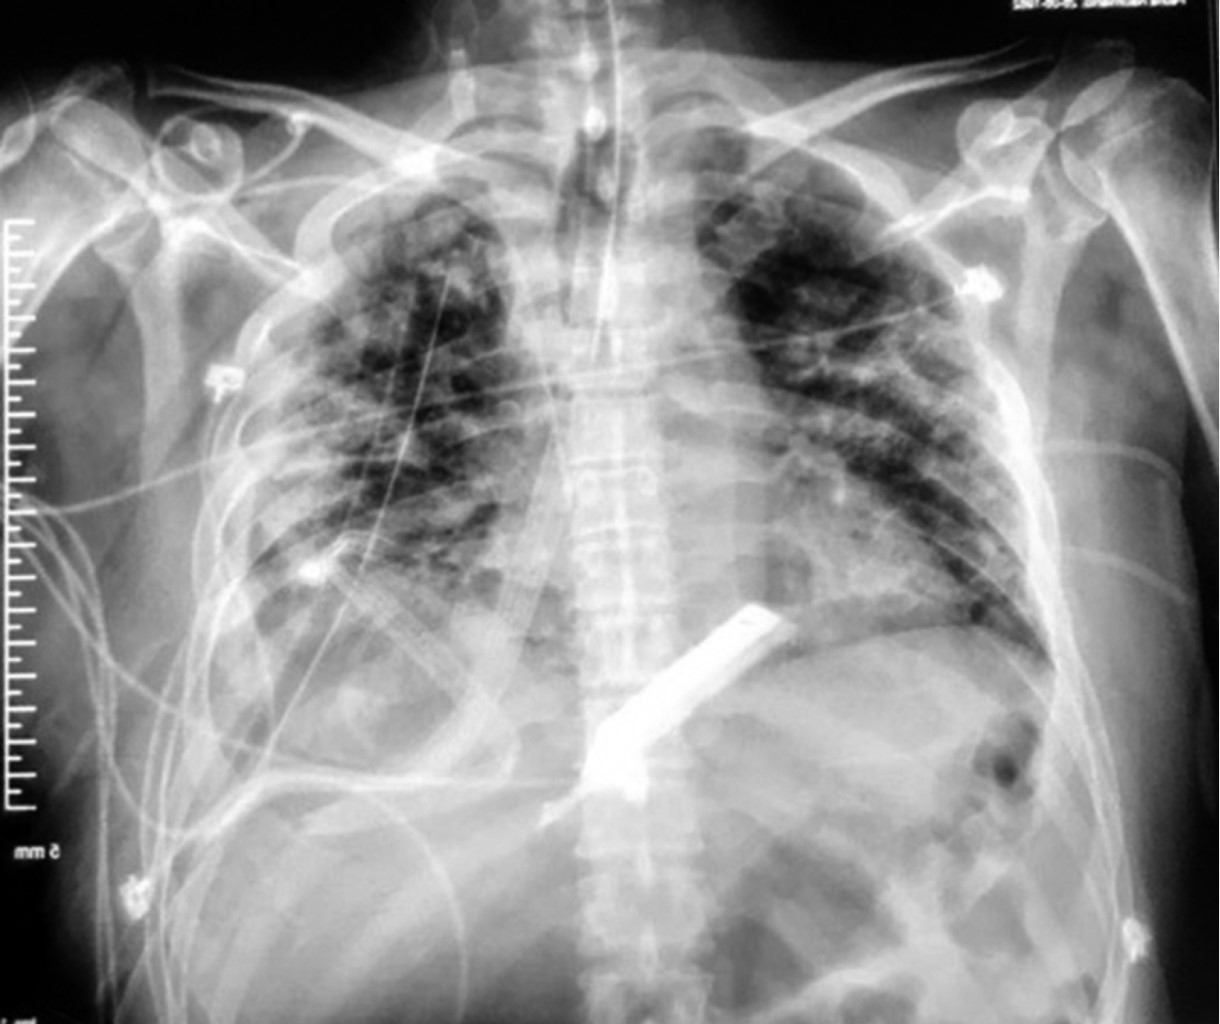

Sin embargo, el paciente evoluciona de manera tórpida, sin lograr reexpansión pulmonar, por lo que se presenta para toracotomía posterolateral derecha el 10-06-20 observando como hallazgos transoperatorios neumonía necrotizante, fístula broncopleural del lóbulo medio derecho y paquipleuritis (Figura 2); se drenaron aproximadamente 200 cm3 de material turbio, se enviaron cultivos y se dejan como drenajes una sonda endopleural y dos drenajes tipo Jackson-Pratt, uno anterior y el otro posterior (Figura 3).

El paciente progresa hacia la mejoría, se decide retiro de sonda endopleural el 15-06-20; es extubado el 18-06-20 y se retira drenaje de Jackson Pratt anterior el 19-06-20. Egresa a domicilio el 23-06-20 para continuar seguimiento por consulta externa.

Figura 3